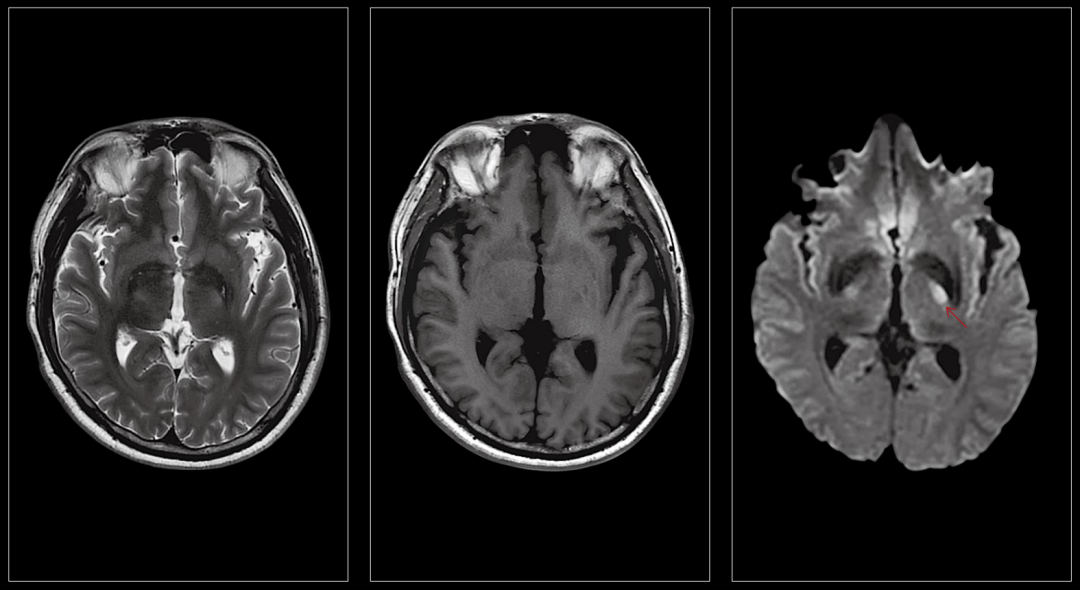

1、神经系统病变

对脑梗塞、脑肿瘤、炎症、先天畸形、外伤、头颈血管壁高分辨率成像及功能成像更清晰,对病变的定位、定性诊断更准确、更及时,可发现早期病变。

急性脑梗塞

头颈部动脉成像